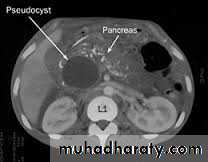

• PANCREATIC PSEUDOCYSTS

• Collection of amylase rich pancreatic fluid enclosed in a wall of fibrous or granulation tissue• Develops in

• Acute pancreatitis

• Chronic pancreatitis

• Pancreatic trauma

Investigations

• US abdomen:size and thickness of cyst

• CT scan:size,shape,number,wall thickness,extent of necrosis,calcification,regional vessels